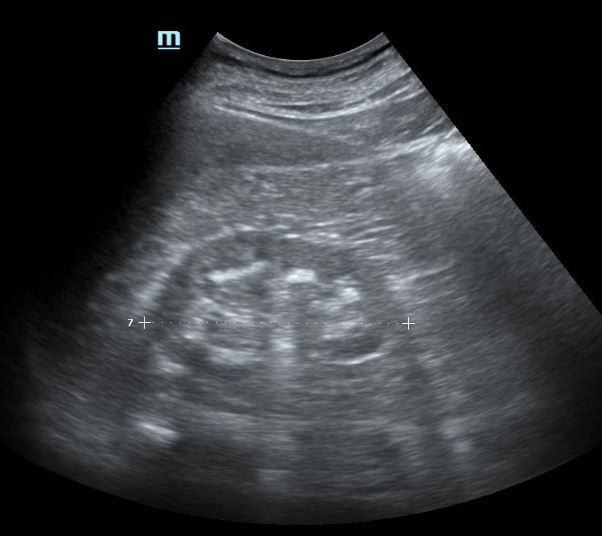

(1)肾实质病变引起的高血压患者中,以尿毒症、慢性肾小球肾炎、狼疮性肾炎等多见,超声可以直观的观察肾脏体积的变化、肾皮质厚度、肾实质回声、彩色血流信号等以判断肾实质病变的进展;多囊肾、肾肿瘤等异常占位性病变,超声可以准确的判断占位大小、形态、血流等情况,为治疗提供可靠的依据。肾脏实质病变多伴有肾血管性病变。

图1